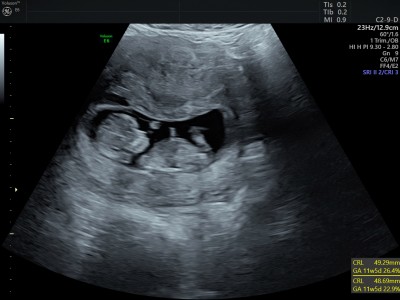

11+5 iken doktora gittim kemik ölçümleri filan yapıldı iki bebeğim olucak doktor birini kıza benzetti kız olabilir dedi resimler elime sonra geçti sizce hangisidir anlayan var mı cinsiyetten?

Gebelik haftası 12+4